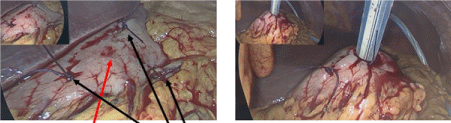

Laparoscopy was performed. The pigtail drain was removed, and 4 stomach wall defects were noted (Figure 2). There was minimal contamination. Gastric acid bubbles were detected on the surface of the liver and in the abdominal cavity. Three of the defects were repaired with 3-0 vicryl and another defect was enlarged for insertion of a 24Fr Stamm gastrostomy tube. Water was injected into the balloon, a vicryl purse string deployed at the stomach surface and the tube was delivered to the skin.

Figure 2. Defects in stomach wall encountered after unsuccessful radiological placement of PEG feeding tube repaired. The black arrow shows 3 repaired stomach wall defects. The red arrow show the stomach wall defect selected for placement of Ped tube entry. The Stamm feeding tube placed in widened stomach wall defect before delivery onto skin surface